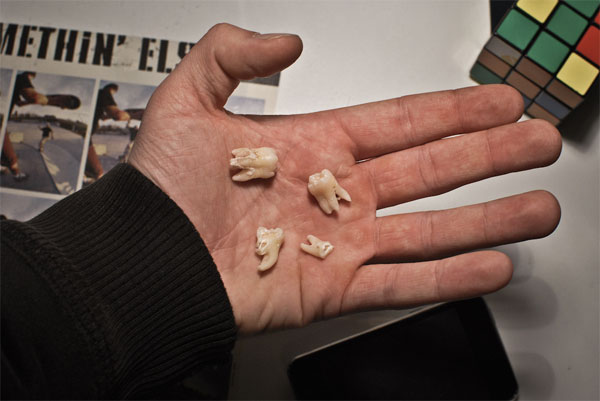

在這些情況下,你應該要拔智齒:牙齒完全藏在牙齦下,不能生長出來,破壞相鄰牙齒的根部;難以清潔,積累細菌;沒有充足空間,傷害到其他牙齒;智齒四周感到痛楚;智齒附近軟組織常常受感染;腫瘤形成;牙齦發炎;相鄰牙齒或智齒蛀牙;沒有對咬牙等等。

如果你有定時看牙醫,也有做過X射線檢查的話,其實是可以不用拔掉健康智齒的。不過在這種情況下,您要先提前了解可能發生的問題,像如果未來有不正確智齒生長的話,需要做手術拔掉它。牙醫也建議,如果要拔智齒,應盡快去做。因為25歲以後,骨骼組織成形,會使牙齒更難拔除,組織癒合得更慢。